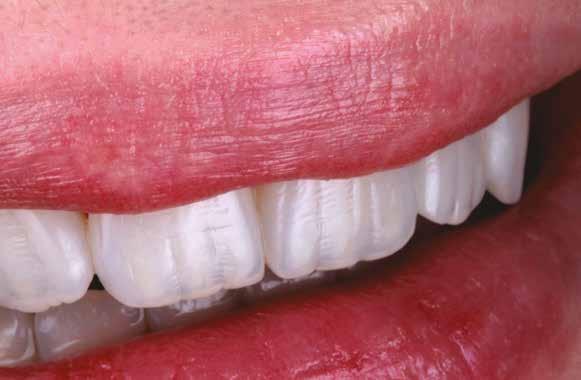

A fogászati kezelések során manapság már nem kizárólag az esztétikai megjelenés helyreállítására törekszünk. Sokszor a kedvezőtlen esztétikai megjelenés hátterében álló okok következményes módon a fogazat funkcionális működését is károsítják, így a kezelések során ezeknek a helyreállításával is foglalkoznunk kell. A különböző funkcionális és esztétikai diszkrepanciák kezelésére számtalan módszer létezik, ám ezen fogászati beavatkozások mindegyikében közös, hogy a kivitelezésük során nagyon szoros együttműködésre van szükség a kezelést végző fogorvos és a munkáját segítő fogtechnikus között. Az alábbi esetbemutatás során egy fiatal hölgypáciens fogazatának héjak alkalmazásával történő esztétikai és funkcionális rehabilitációját szeretnénk ismertetni.

A kezelés során az jelentette a legnagyobb kihívást, hogy a héjakkal ellátott fogak élethűen utánozzák a természetes fogazat megjelenését. A fogpótlás színének, valamint a restaurátumok felszíni textúrájának és alakjának harmonikusan kell a páciens arcesztétikájához és karakteréhez illeszkednie.

nak megfelelően – előkészítjük (orthofoszforsavval történő savazás, lemosás, szárítás és bond réteggel történő fedés). Ezzel egyidejűleg a ragasztásra kerülő héjak is előkészítésre kerülnek (hidrofolysavval történő savazás, lemosás, szárítás, szilanizálás, bond réteggel történő fedés, és végül az alkalmazni kívánt ragasztóanyag felvitele). Ezután a héjakat a fogak felszínén egyesével pozicionáljuk, majd néhány másodpercen keresztül polimerizációs lámpa segítségével megvilágítjuk. Ezt követően a kifolyó ragasztófelesleget eltávolítjuk, majd elvégezzük a restaurátumok végső polimerizálását. A héjak végleges rögzítését követően az esetlegesen visszamaradt ragasztómaradványok eltávolításra kerülnek, valamint ellenőrizzük az okklúzió és artikuláció közben létrejövő fogérintkezéseket. Az optimális esztétikai eredmény biztosítása érdekében kiemelt jelentősége van a papillák helyreállításának (rózsaszín esztétika). A modern fogorvoslás egyik kiemelt célja a fehér- és rózsaszín esztétika közti harmonikus egyensúly megteremtése. A papillák színe, nagysága és szimmetrikus megjelenése meghatározó szerepet tölt be a rózsaszín esztétika kialakításában. Az íny lefutása ugyancsak rendkívül jelentős mértékben befolyásolja a páciens fogazatának esztétikus megjelenését.

A cikkünkben bemutatásra kerülő eset ellátása során preparációt nem igénylő héjak készítése mellett döntöttünk. A héjak készre vitele során a platinafólia technikát alkalmaztuk. Annak ellenére, hogy az elkészítésre kerülő héjak rendkívül vékonyak, és ezáltal a végleges rögzítésük előtt jelentős törésveszéllyel állunk szemben, összességében mégis olyan minimál invazív kezelési eljárásnak számítanak, amely segítségével kifogástalan esztétikai eredményeket lehet elérni. A fent leírtak alapján bátran javasoljuk e módszer alkalmazását.